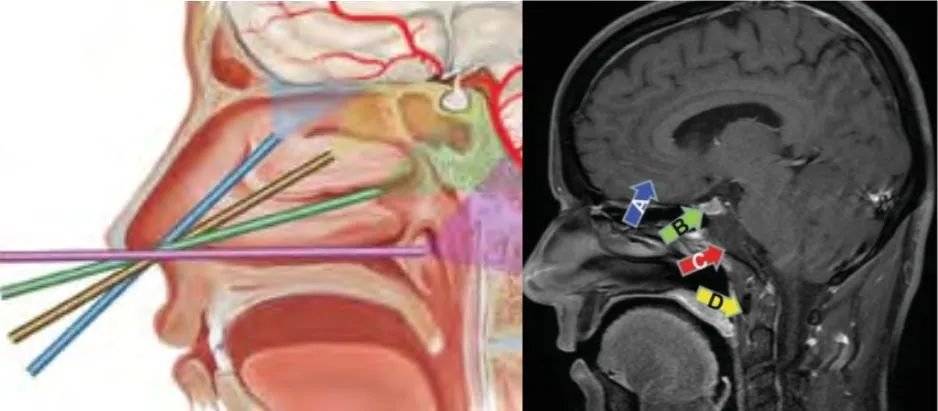

随着我们医学技术的进步,现在许多的颅底肿瘤可以采取内镜经鼻入路的方式完成。为什么可以这样做呢,我们再打个形象的比喻,我们的鼻窦位于颅底的下方,采用经鼻方式进入颅底,就是在我们脑袋这个房子的地板上凿了一个洞,我们从地板下方将神经内镜通过这个洞来切除肿瘤(图1)。

图1内镜经鼻入路至颅底